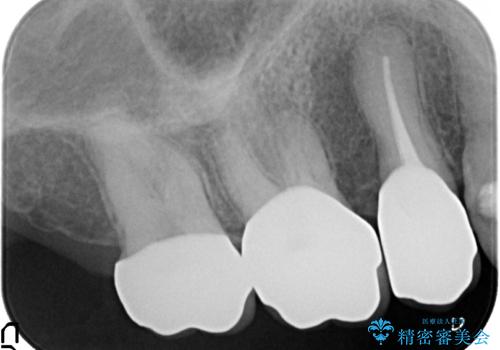

- 右上の奥歯がしみるので診て欲しいといらっしゃった方の症例です。

診査の結果痛みの原因は右上7番目だったため、古い樹脂と虫歯を除去後、オールセラミッククラウンによる補綴を行いました。

また右上5、6番目の歯も治療を希望されたため、オールセラミッククラウンによる補綴を行いました。

- オールセラミッククラウン…¥100,000×3、仮歯…¥10,000×3、ファイバーコア…¥20,000費用は治療当時の料金となります